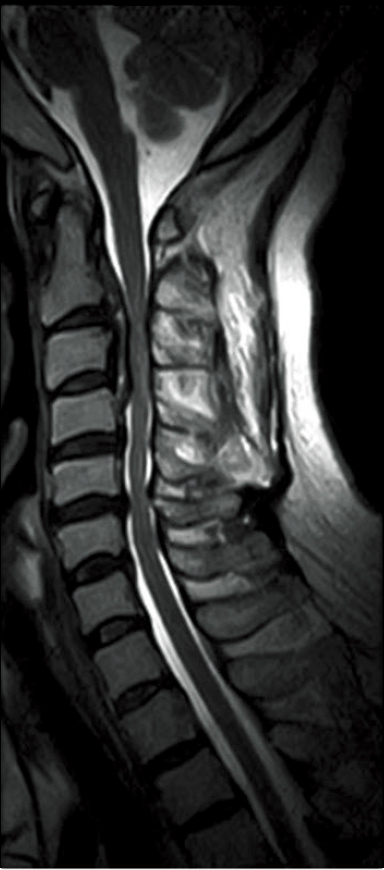

T2WI